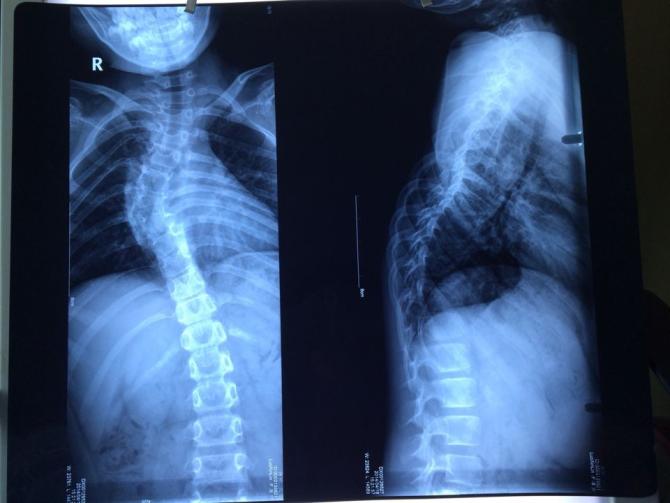

- 检查片子

小鑫林从七岁开始,家人就觉得她脊柱有点不正常,便立即带孩子到常德市第一人民医院检查,小鑫林被查出患有脊柱侧弯。这个消息当时让家人不敢相信。为了给孩子及时的治疗,当时家人就花了四五千给鑫林佩戴了矫形支具。但是配戴两年后,畸形并未明显矫正。反而越来越严重。

因为家庭贫困,孩子未能得到及时的治疗,病情也越来越严重。2014年2月,在爱心志愿者的帮助下,孩子先后在湖南省常德市第一人民医院、湖南湘雅二医院、北京协和医院进行了详细的复查,最终诊断为脊柱侧弯及后凸畸形,病情越来越严重,医院建议鑫林必须尽早进行手术治疗,至少要进行费用总计将会达到40万。